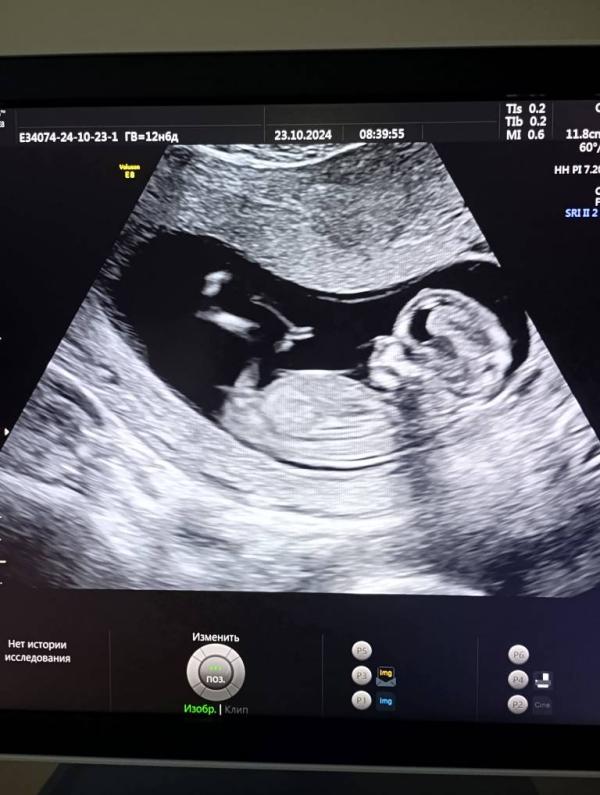

Первый скрининг пройден: малыш машет руками и ногами! Патологий нет, ждем чудо!

А вот и мы сегодня ходили на первый скрининг, врач смеялась сказала язык показывает и руками и ногами машет😘😍все хорошо патологий нет ,ждем тебя наше чудо!